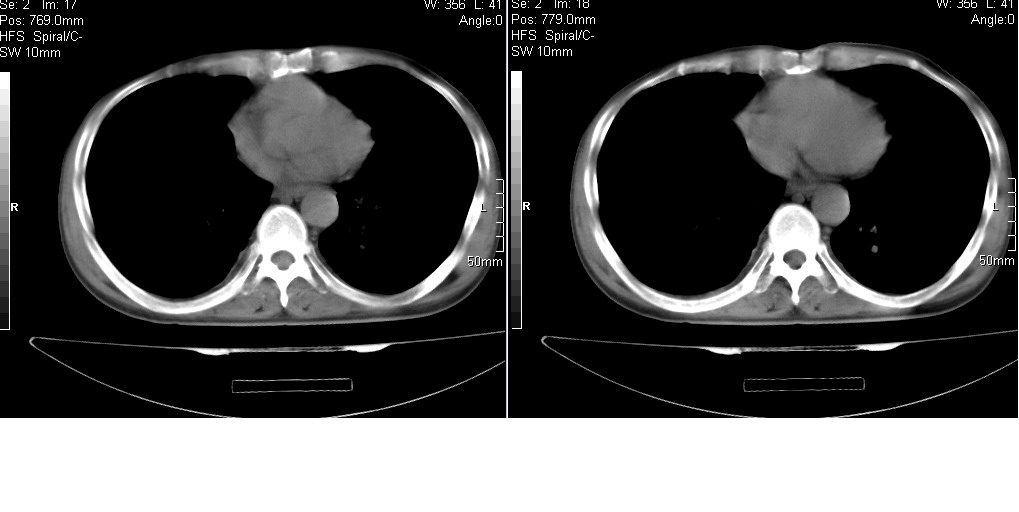

以下是引用光线在2008-5-6 18:36:00的发言:[br]双肺结核(左上肺空洞形成)、间质性改变合并感染,右肺大泡;右侧胸膜增厚。

以下是引用zsl6918在2008-5-7 1:54:00的发言:[br]首先肺泡蛋白质沉着症,其次考虑机遇性感染。